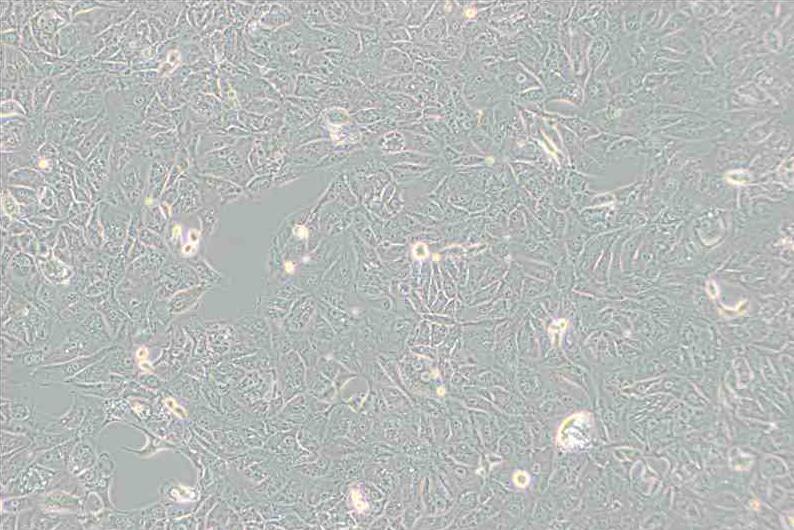

上皮细胞样

背景描述769-P细胞来源于原发性透明细胞腺癌;769-P细胞呈边界不清楚的球形、高核质比、有微绒毛和桥粒;769-P细胞可以在软琼脂中生长。

细胞形态上皮细胞样